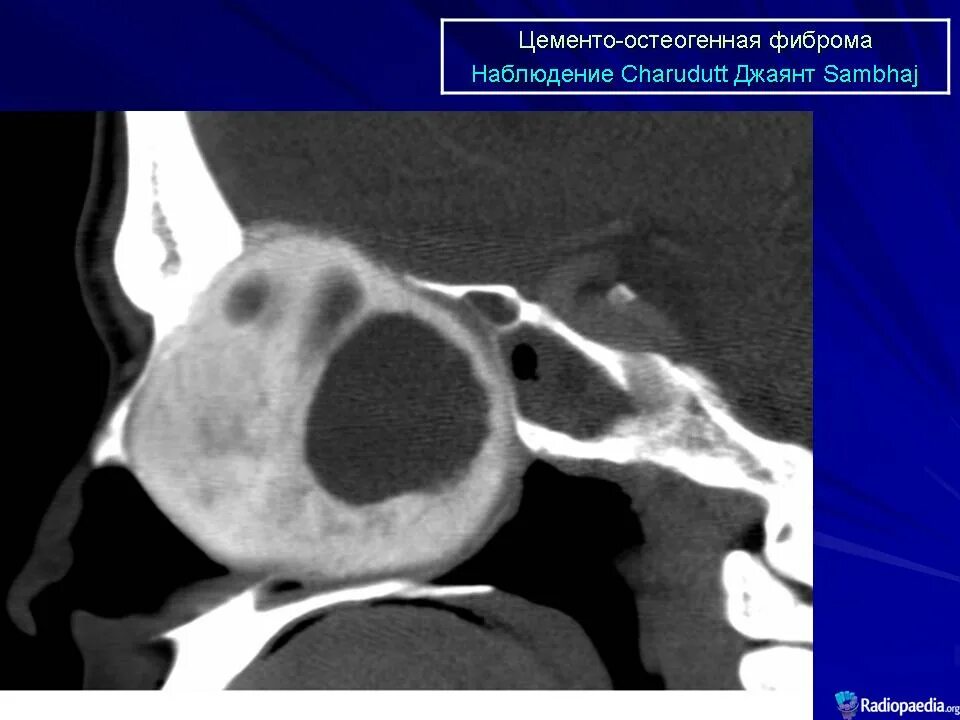

Фиброма кт